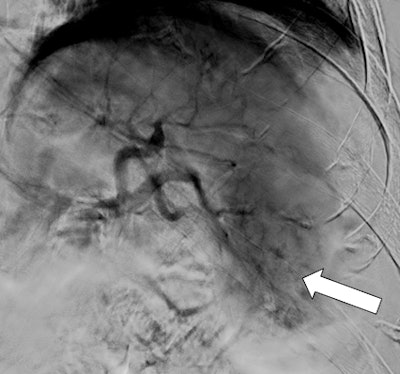

Splenic arteriogram demonstrated parenchymal injury and active extravasation, which corresponded with the CT, with identifiable contrast extravasation (figure 3A). In a location distal to the dorsal pancreatic artery, SAE was performed utilizing 0.035- and 0.018-inch coils.

More than 35 coils were used to reach stasis because the splenic artery was hypertrophic with a very robust flow. Postembolization control arteriogram was performed and confirmed stasis of flow within the mid and distal splenic artery (figure 3B). The patient's hemoglobin stabilized; he clinically improved and was subsequently discharged.

Our patient was managed according to the spleen trauma management algorithm for adult patients and underwent SAE for splenic injury with active extravasation seen on CT abdomen scans with IV contrast and splenic artery angiography. Care was taken to avoid the dorsal pancreatic artery as seen in figure 3; however, more than 35 coils were used to bring about stasis of blood.